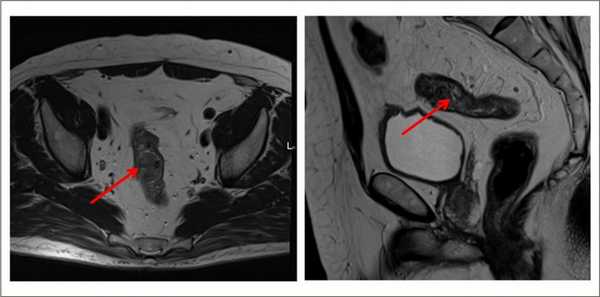

Выявляет даже небольшие по размеру патологические очаги, метастазы и инвазию опухоли в соседние органы, ее топографическое положение относительно других структур. Метод безопасен, не создает радиационную нагрузку, в отличие от КТ.